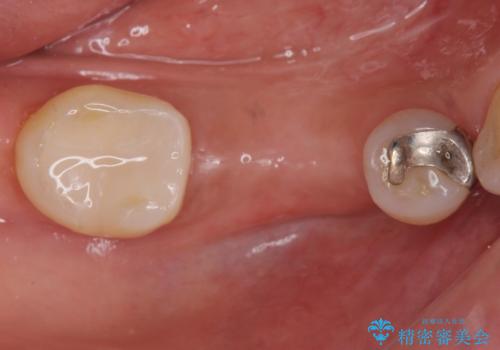

保存できない状態でしたので抜歯をして歯槽堤保存術を行いました。その後大臼歯部にインプラント治療を行いました。

欠損部に1本だけインプラントを埋入しても大きな被せ物になってしまい清掃性が悪くなるので清掃性が良くなるように2本小臼歯用のインプラントを埋入しました。